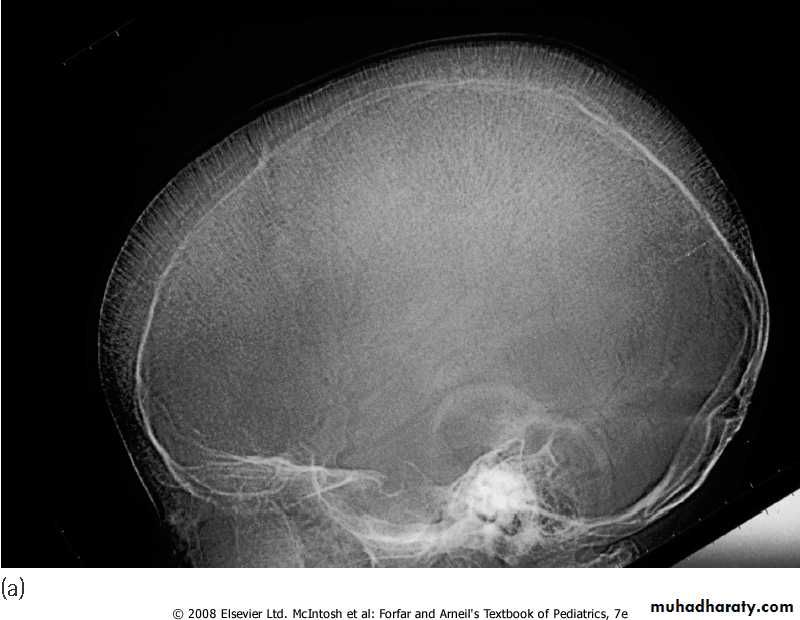

4. BM hyperplasia is seen in bone XR.

Skull X-ray showing ‘hair on end’ appearance caused by marrow hyperplasia and expansion